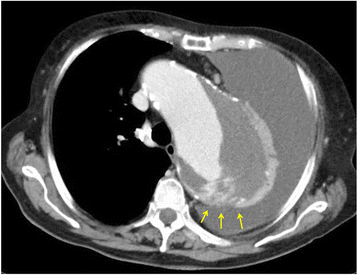

In patients with suspicion of aortic rupture, plain CT is also useful to detect fluid effusion in the pleural cavity or pericardial space, and information regarding whether a hematoma exists around the aneurysm is useful in making the diagnosing aortic rupture. In such cases, CT with contrast media should be performed to detect the presence of contrast leaks (Fig. 4). Even with clear findings of hematoma around the aneurysm, contained or impending rupture of an aortic aneurysm is an indication for urgent treatment because of the risk of subsequent rupture [1]. Once acute aortic dissection is confirmed, it is also important to know the condition and quality of the iliac and femoral arteries because the surgical approach, including endovascular treatment, is affected. To perform endovascular treatment, anatomical factors, including the presence of adequate proximal and distal landing zones for the prosthesis, should be assessed simultaneously [26].